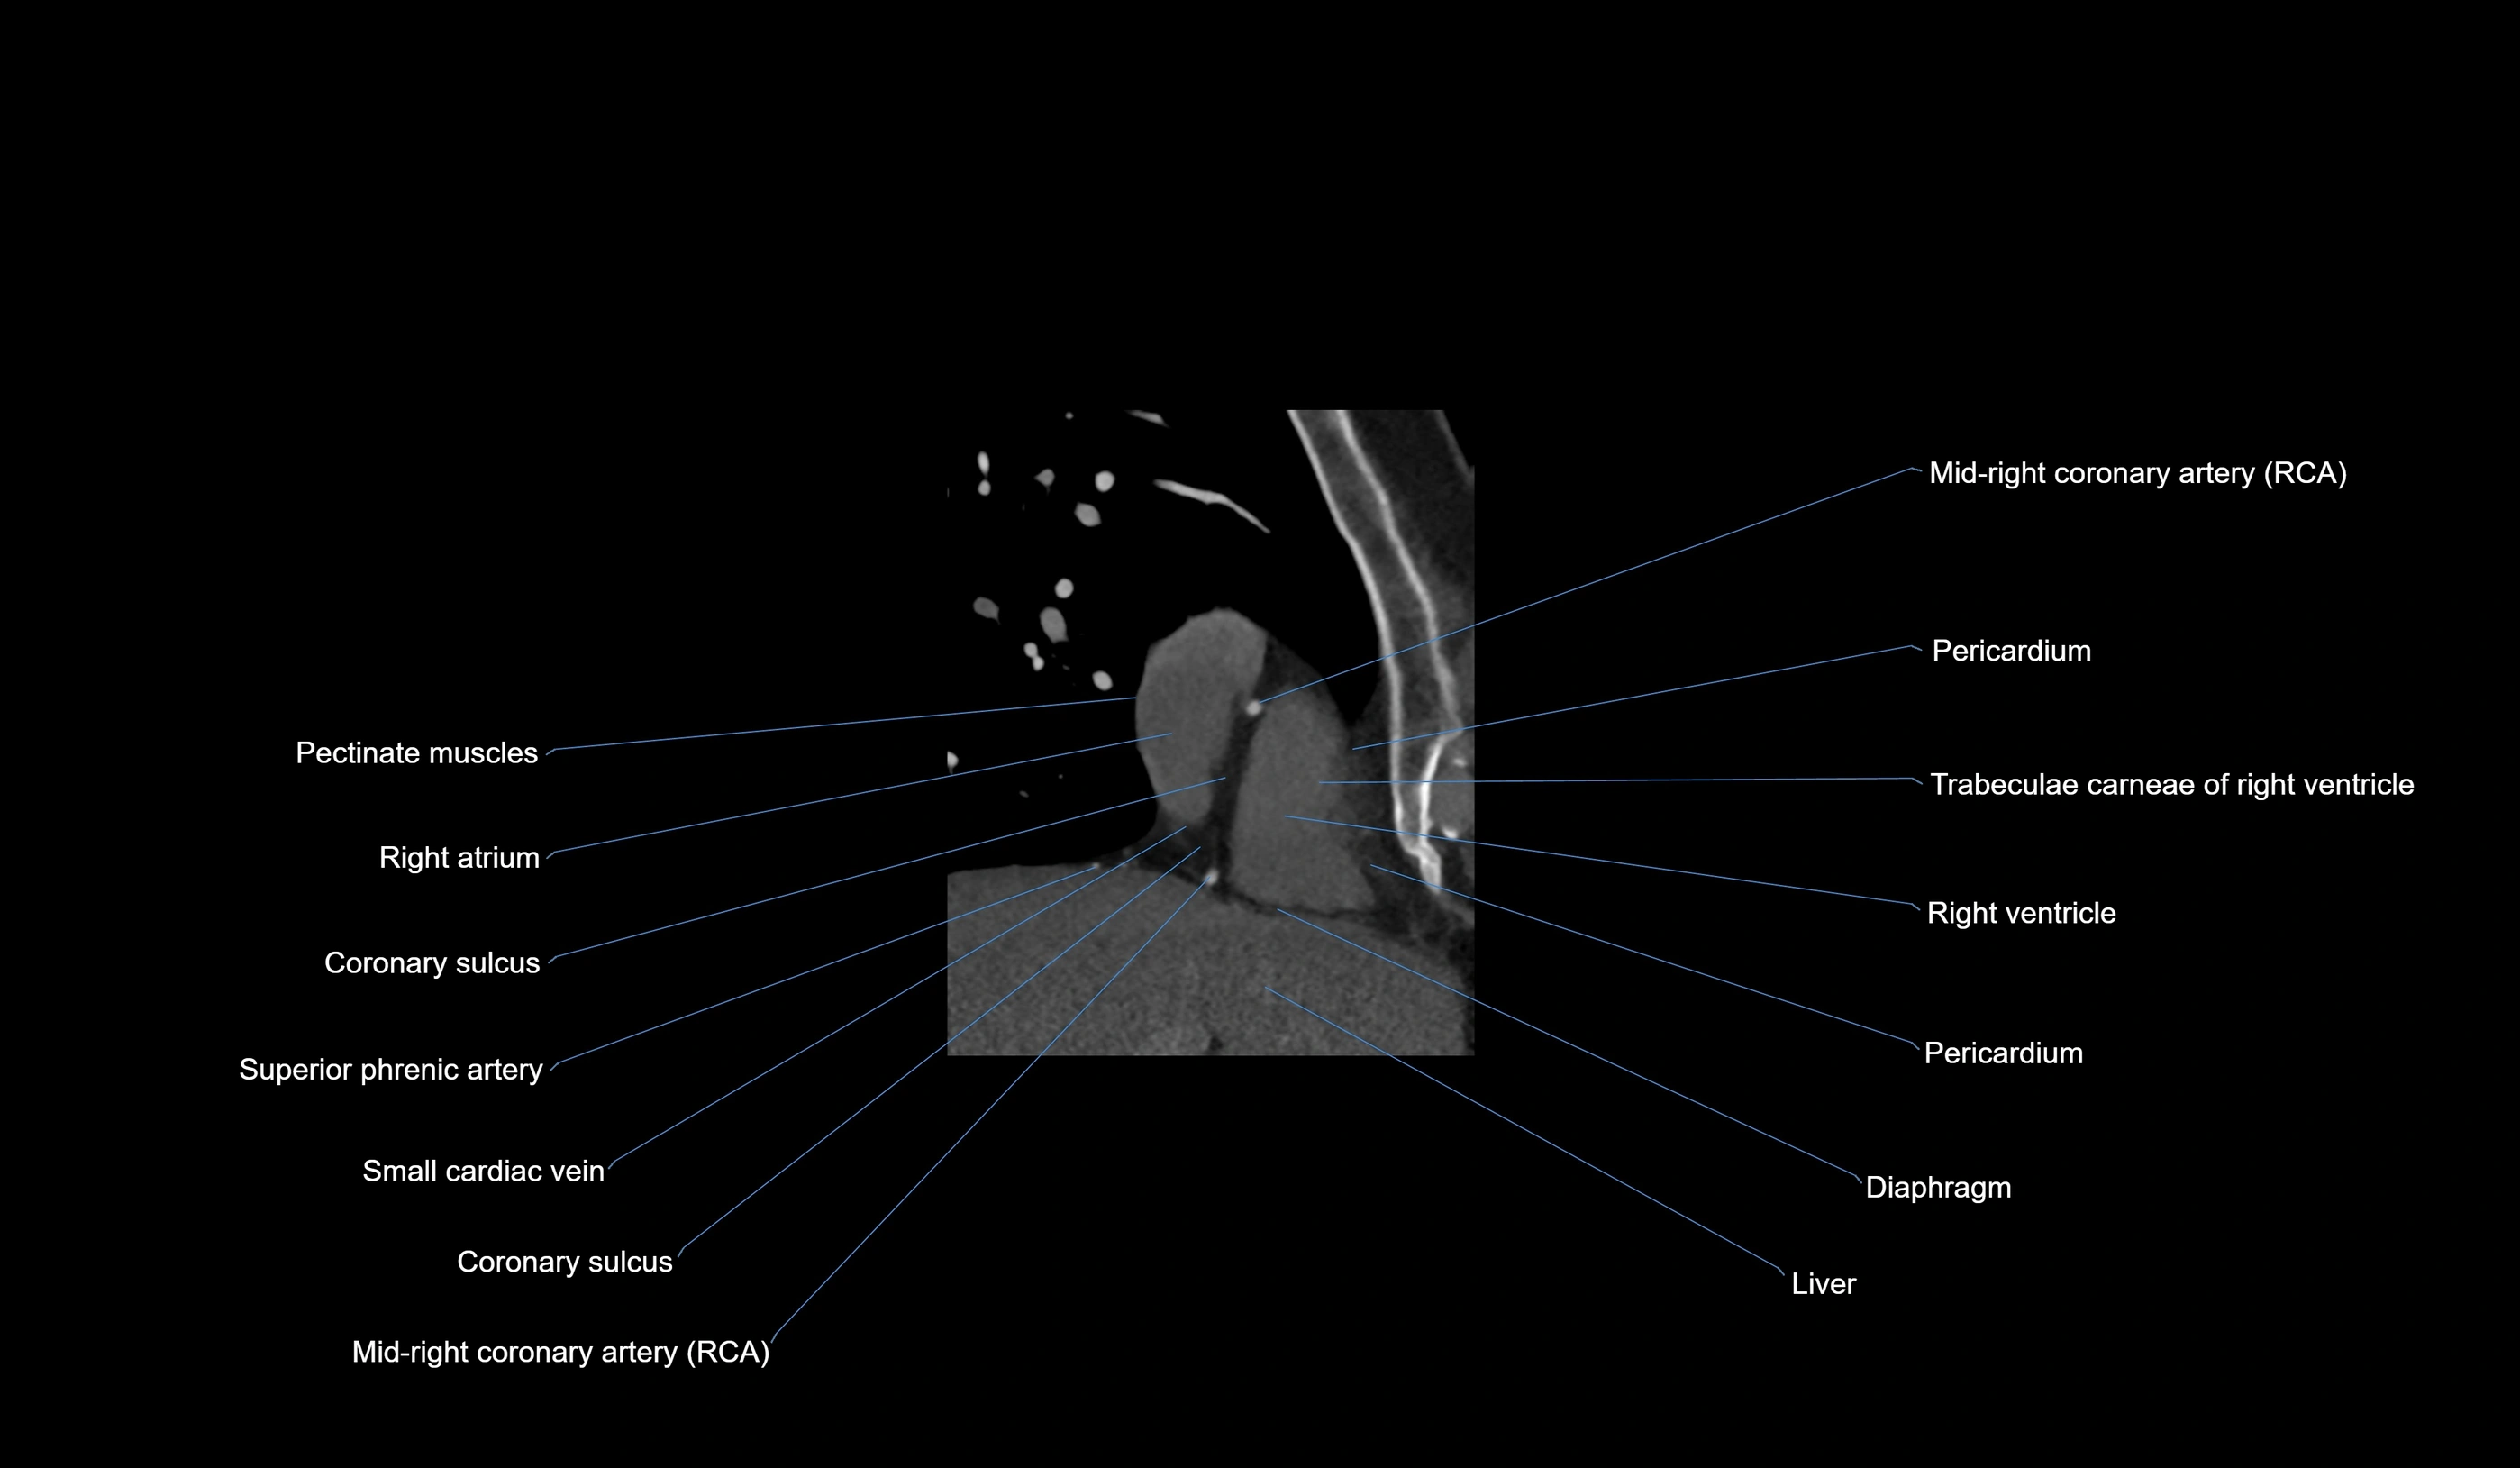

- Right coronary artery (RCA)

- Right posterior descending coronary artery (Right PDA)

- Small cardiac vein

- Coronary sulcus

- Pectinate muscles

- Right atrium

- Right ventricle